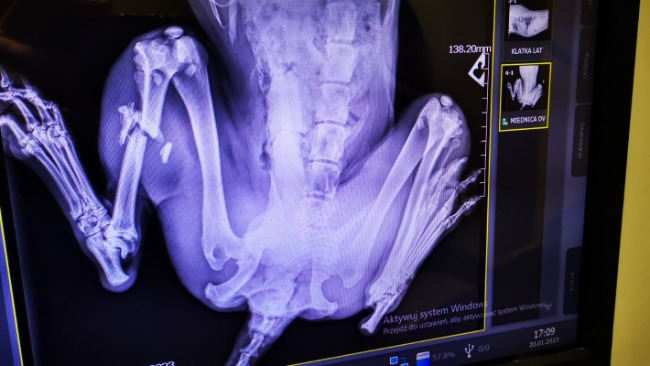

Młody dzieciak, który tygodniami błąkał się po ulicach Garwolina, w międzyczasie potrąciło go auto druzgocząc mu łapę i wyrywając dziurę w skórze.

W dniu 22/01/2023 Zuch ma być operowany w klinice na Bemowie, przez dr Krajewskiego. Koszt operacji to około 3500 zł

Do tego dochodzą 3 doby szpitalne po 400 zł każda plus badanie krwi, kału i leczenie mikrofilarii, razem około 5500 zł...